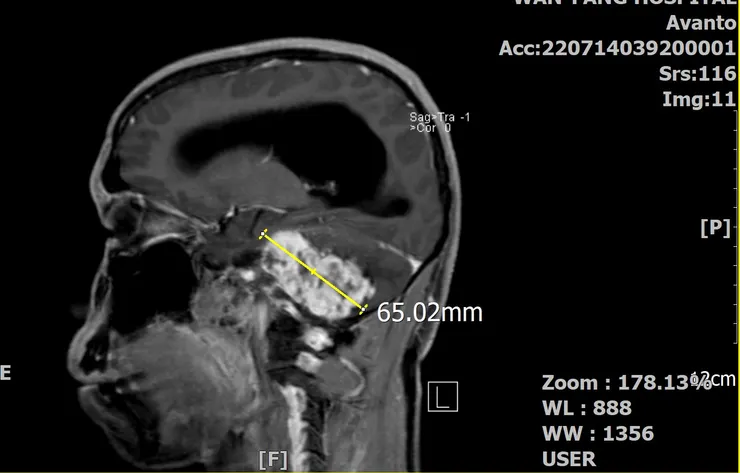

椰當年在MRI下的龐大身軀(矢狀剖面)

當時的椰已經6公分了,這體積早把我的腦幹都「擠歪」了。影響最的的是聽力跟平衡的狀況,於是我逐漸失去了左耳的聽力,以及走在亂石堆的郊山步道上,總是很怕跌倒(不是體力差)。